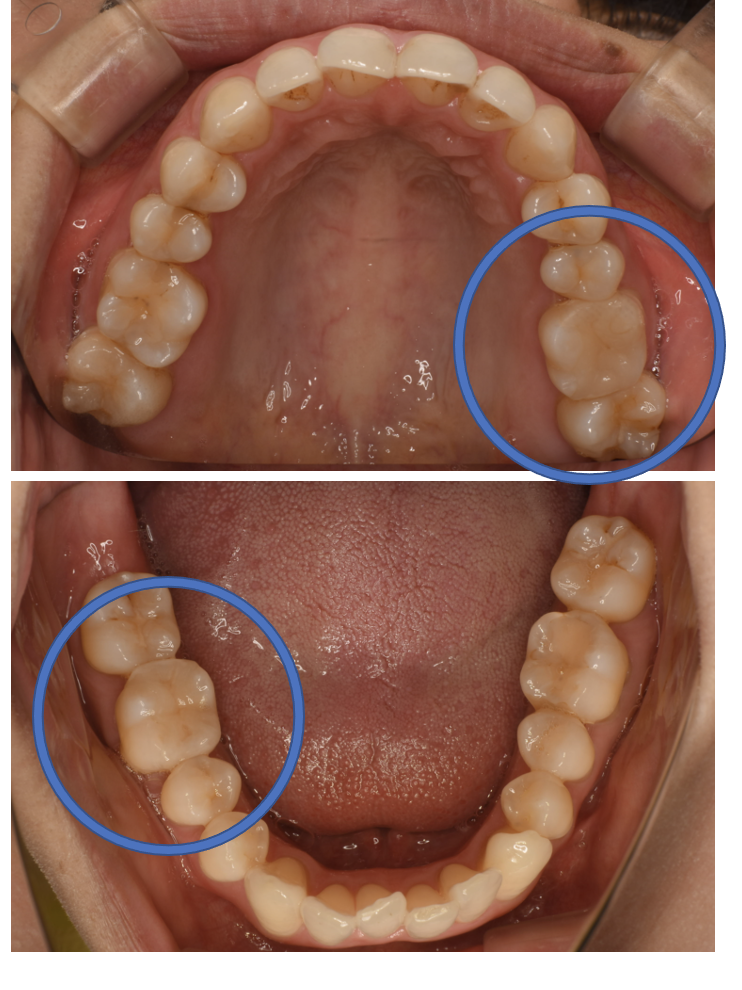

E-max In詰め物

E-max In 10 + フルジルコニアCr No.66

Before

After

| 治療方法 | セラミックインレー(E-MAX In)、ジルコニアCr 虫歯などで失った歯質を天然歯と同じ色・質感のセラミックで補う治療法です。金属を使用する治療と比べて、審美性だけではなく、耐久性や体の負担が少ないという面でも優れていると注目されています。従来のセラミックと比べて天然歯と同程度の強度であり、耐久性が高くなっています。どのくらいもつかは使用状況や部位、メンテナンスの有無などによって大きく変わってきます。透明感があり、キレイで自然な色調を表現できます。歯と分子レベルの化学結合によって吸着するため隙間ができることが少なく、虫歯にもなりにくいと言われています。 そして、金属アレルギーのリスクがありません。 |

| 費用 | ¥89,000×2本+¥69,000=247,000 |

| 通院回数 | 1ヶ月〜6ヶ月 |

| 備考 | 院長より 銀歯の内部に虫歯が進行してしまっていたケースです。中を開けて見てみると、外から想像するよりもはるかに虫歯が広がってしまっていました。幸運にも神経を保存できたので、生きた臓器としてまだ使うことが可能です。残存歯質がかなり薄く弱くなってしまったので、ジルコニアで被せて守ってあげています。反対側の歯は、残念ながら虫歯の進行が神経まで及んでいて、根の治療が必要になってしまったケースです。そして、一本、銀歯の内部で虫歯が進行しすぎていて、抜歯せざるを得ない歯がありました。部分的なセラミックで詰めている歯も一本あります。 |